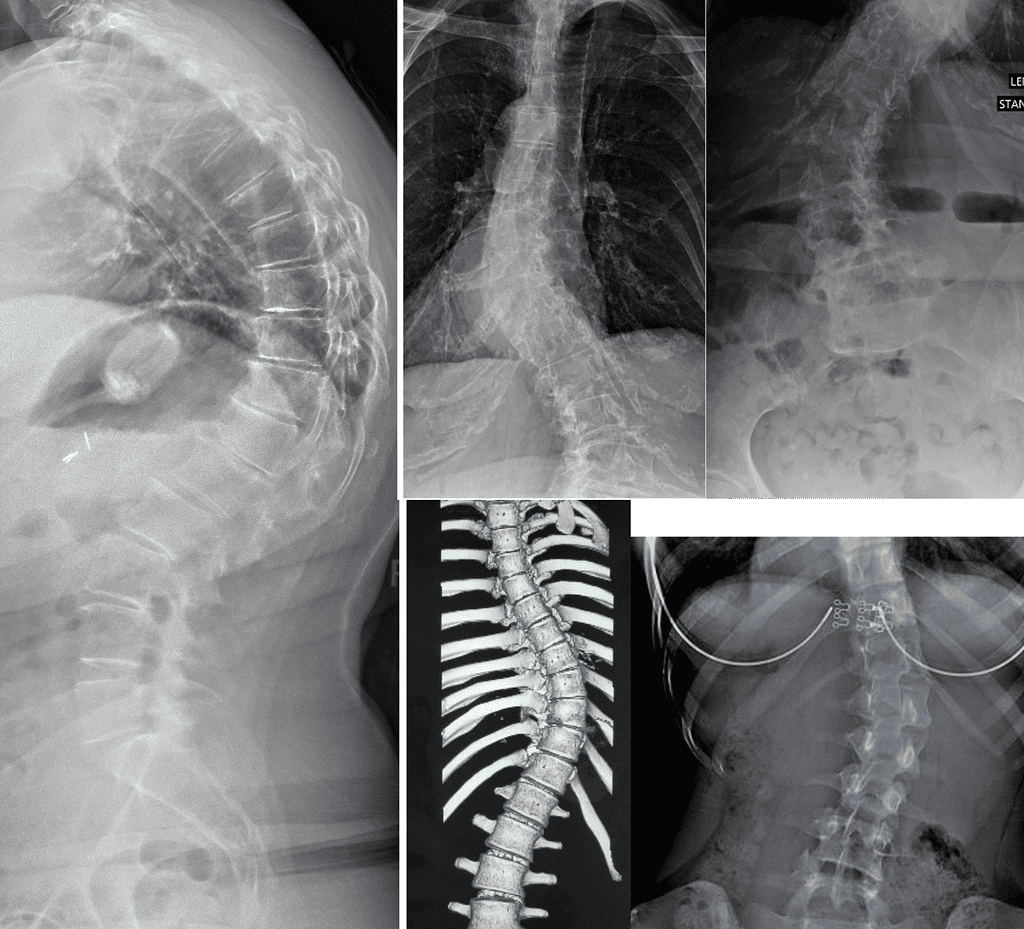

Measurable outcomes on X-ray. Here is what our co-managed patients have experienced.

Note: Individual results vary. All measurements taken on calibrated standing AP radiographs by the treating doctor. Cases shown with patient/guardian consent.

In-Brace Correction is normally 48% but we could see 63%.*

Out-of-Brace curves achieved 37.60% improvement if their curves are 20°-40°.

Results: curve correction: 76.9%, curve stabilization: 23.1%, curve progression 0%